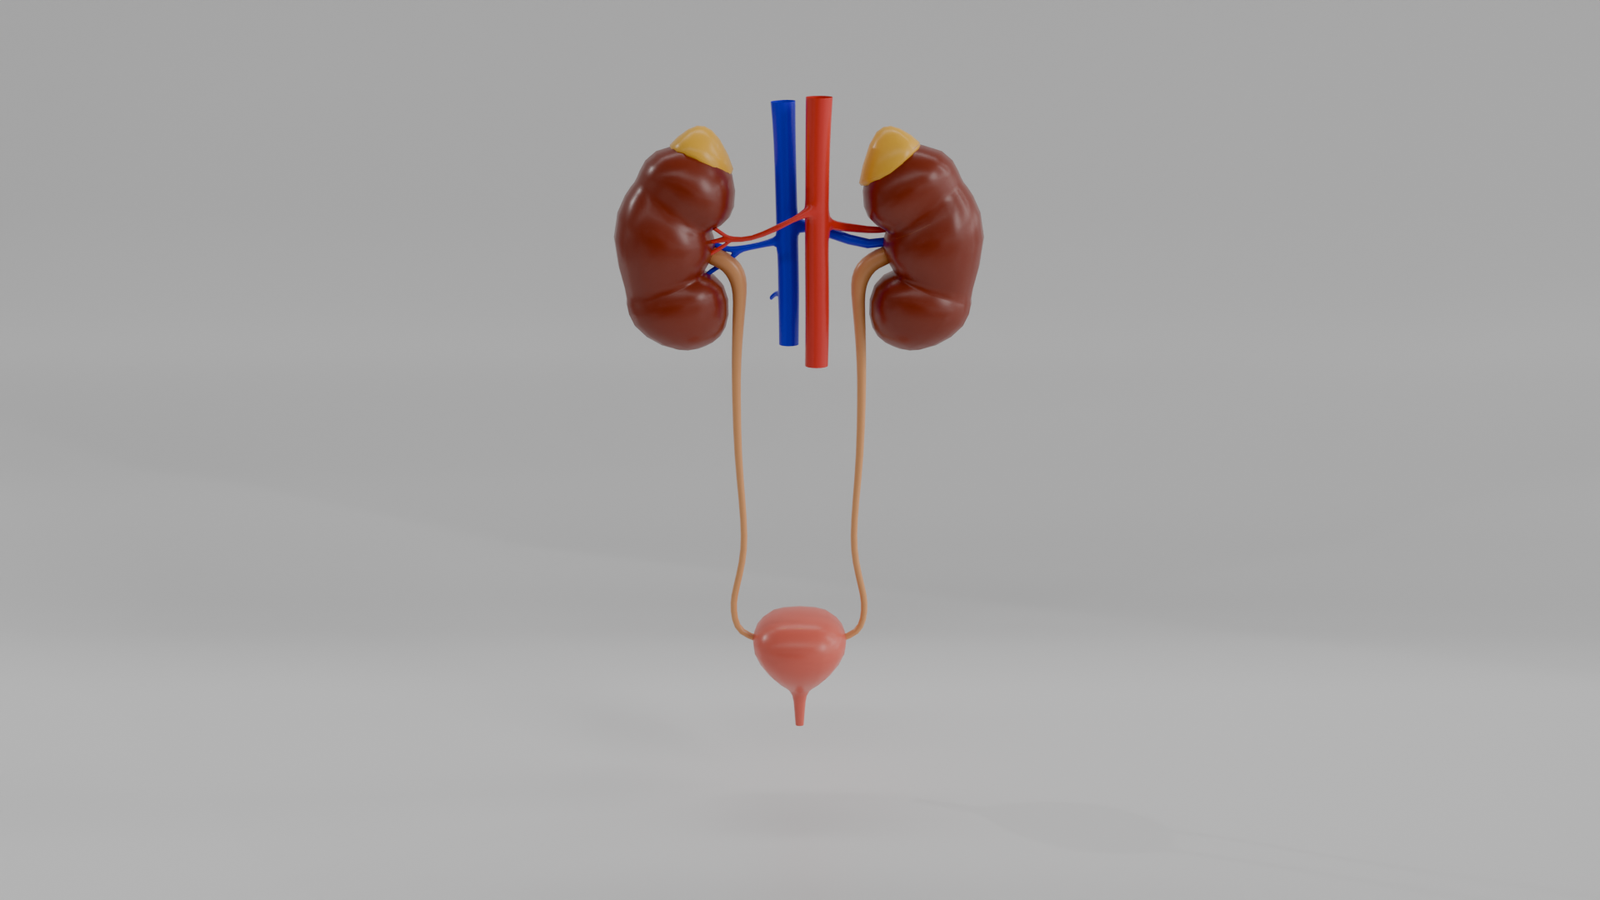

Riñones

Modelo 3D educativo